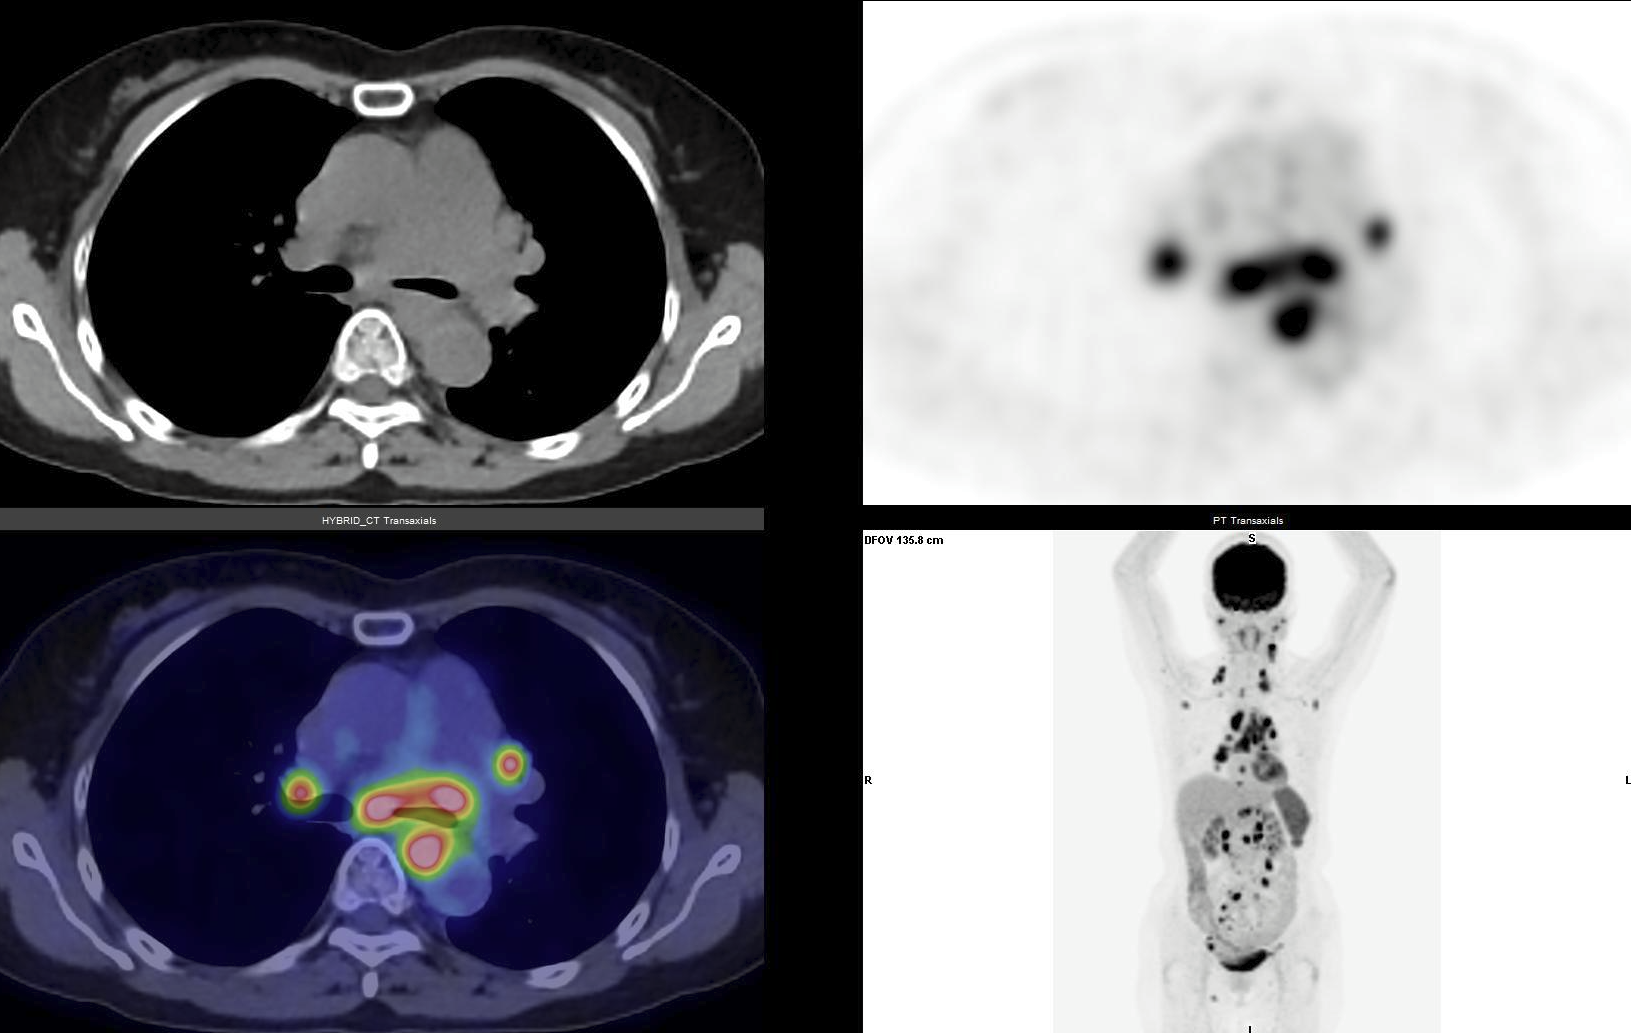

Hình ảnh FDG PET/CT ở bệnh nhân lymphoma kiểm tra định kỳ sau 1 năm điều trị, ghi nhận nhiều tổn thương tăng hấp thu FDG gợi ý tái phát bệnh. Ảnh: BVCC

Trong khi siêu âm, X-quang hay CT chủ yếu phản ánh hình thái giải phẫu, hình ảnh y học hạt nhân cho phép phát hiện những thay đổi về chuyển hóa và biểu hiện thụ thể của tế bào ung thư từ rất sớm, trước khi tổn thương có biểu hiện rõ về mặt cấu trúc.

Các kỹ thuật của y học hạt nhân sử dụng dược chất phóng xạ để ghi nhận sự phân bố và chuyển hóa trong cơ thể. Nhờ đó, bác sĩ có thể phát hiện những ổ tổn thương tái phát ngay từ giai đoạn sớm, tạo điều kiện để điều chỉnh phác đồ điều trị kịp thời và nâng cao tiên lượng cho người bệnh.

Đặc biệt, trong theo dõi ung thư, PET/CT là kỹ thuật y học hạt nhân được sử dụng phổ biến nhất hiện nay. Với các dược chất phóng xạ như 18F-FDG, 68Ga-PSMA, 68Ga-DOTATATE, PET/CT giúp đánh giá chuyển hóa glucose, mức độ biểu hiện thụ thể hoặc các đặc tính sinh học khác của tế bào ung thư.

Ở nhiều loại ung thư như ung thư hạch, ung thư đầu - cổ, ung thư phổi, ung thư đại trực tràng và ung thư tuyến tiền liệt, PET/CT cho thấy độ nhạy và độ đặc hiệu vượt trội trong phát hiện tái phát so với các phương pháp hình ảnh thông thường.